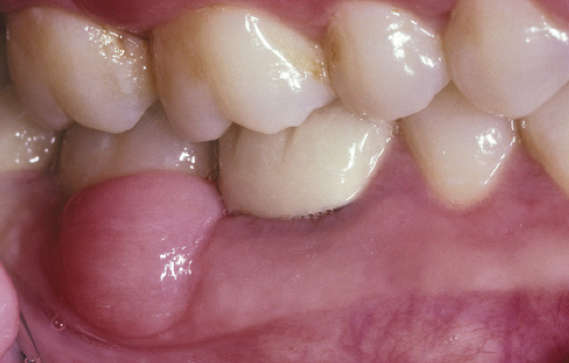

What is the likely Dx?

Peripheral ossifying fibroma.